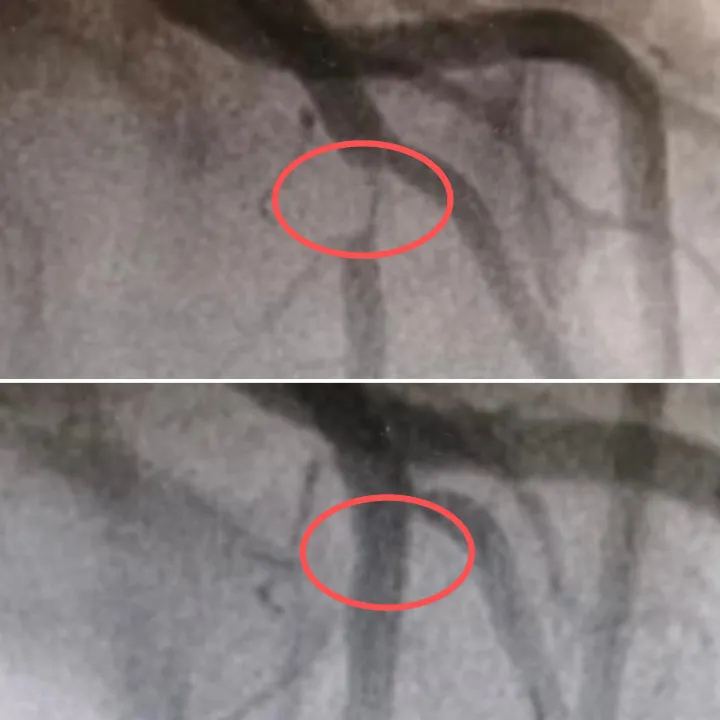

Kết quả chụp mạch máu sau đó khiến các bác sĩ bất ngờ, mạch máu quan trọng nhất trong tim, nhánh động mạch vành trái trước... bị tắc nghẽn đến 95%, chỉ còn một khe hẹp cung cấp máu, và luôn có nguy cơ bị tắc nghẽn hoàn toàn. Mạch máu này giống như "động mạch chính" của tim; nếu bị tắc nghẽn, nó sẽ gây ra nhồi máu cơ tim nghiêm trọng. Hậu quả sẽ không thể tưởng tượng nổi.

Nữ nhân viên văn phòng mới 27 tuổi mà 95% động mạch vành đã tắc nghẽn vì thói quen nhiều người làm mỗi ngày- Ảnh 1.

Các bác sĩ đã tiến hành cấy ghép thành công một stent vào mạch máu bị tắc của Tiểu Vân, mở rộng đoạn mạch hẹp, khôi phục nguồn cung cấp máu cho tim và cứu cô khỏi "bờ vực".